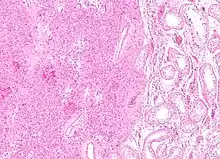

Histopathology of a Leydig cell tumor, high magnification, H&E stain, showing typical features.[1]

A conclusive diagnosis is made via histology, as part of a pathology report made during or after surgery. Reinke crystals are classically found in these tumours and help confirm the diagnosis, although they are seen in less than half of all Leydig cell tumours. Immunohistochemical markers of Leydig cell tumours include inhibin-alpha, calretinin, and melan-A.[6]